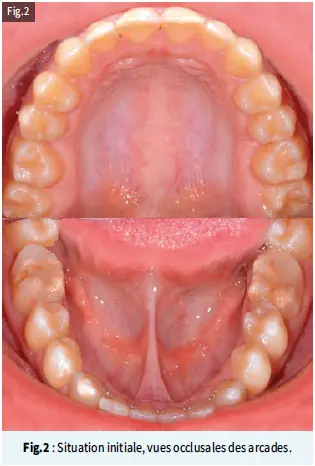

Les premières molaires mandibulaires de couleur brunâtre ont subi une dégradation post-éruptive, avec des restaurations en résine composite atypiques. On observe une asymétrie des défauts en ce qui concerne la localisation et le degré d’atteinte (Fig.2).